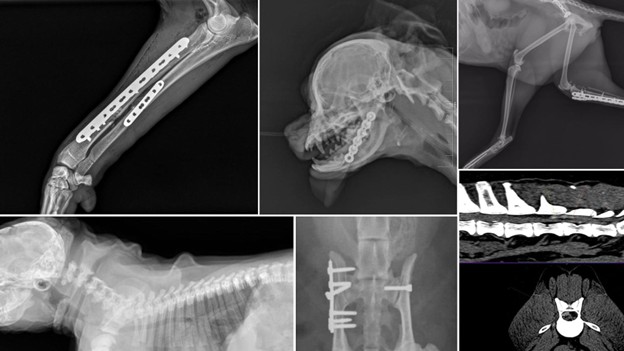

Ortopedia veterinară este ramura medicinii veterinare care tratează afecțiunile aparatului locomotor al animalelor (oase, articulații, ligamente). La Spitalul Veterinar Pet Stuff din București, acest domeniu include servicii specializate de ortopedie canină, ortopedie felină și chiar ortopedie pentru specii exotice, toate realizate conform celor mai înalte standarde. Diagnosticul